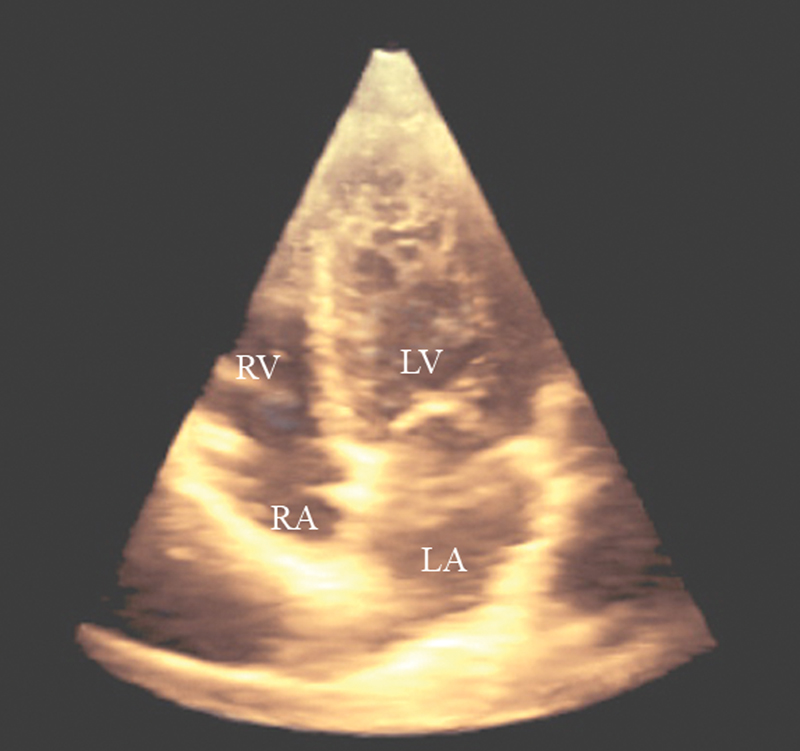

فحوصات تشخيصية لبعض امراض القلب والشرايين التاجية